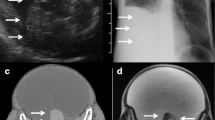

Whilst a mature teratoma or dermoid cyst presents on ultrasound as a cystic lesion with a densely echogenic tubercle (termed a Rokitansky nodule or nidus), which projects into the cystic lumen [3], as well as associated sound attenuation due to sebaceous material and hair within the cyst cavity or recognisable fluid–fluid levels from the sebum floating above aqueous material [3, 23], the ultrasound features of a struma ovarii are quite indistinct (Fig. 3). As struma ovarii presents with a variety of non-specific appearances and usually manifests as a multilocular cystic ovarian mass with solid components of various amounts, the ultrasound typically demonstrates these non-specific heterogeneous solid cystic features [3].

Difference in ultrasound features between struma ovarii and ovarian dermoid cyst. a Predominantly cystic struma ovarii typically mimicking an epithelial ovarian tumour (either cystadenoma or borderline ovarian tumour) in the right ovary of a 51-year-old patient presenting with non-specific abdominal cramps. Some thicker septations are seen (arrow) between otherwise cystic areas presenting with anechoic fluid and posterior acoustic enhancement (A).Right 1.5-cm (b) and left (c) 5.1-cm dermoid cyst in a 24-year-old woman. Both lesions on ultrasound have the typical pattern of high attenuation within the cyst (arrows) representing its fatty component